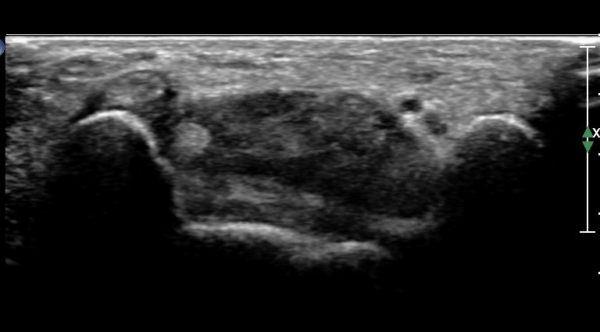

ÃÊÀ½ÆÄ °Ë»ç :  ¼Õ¸ñ¿¡¼­ Á¤Á߽Űæ Ⱦ´Ü¸é°Ë»ç»ó Á¤Á߽Ű泻 °í¿¡ÄÚ Á¾±«°¡ °üÂûµÈ´Ù(»çÁø 1)